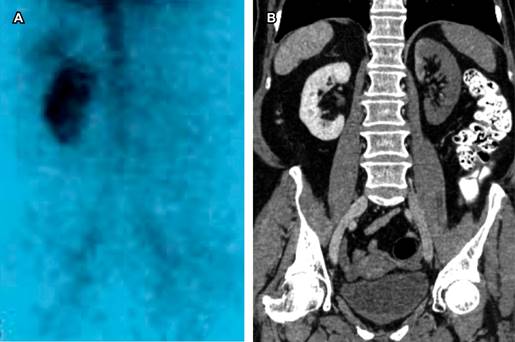

En caso de que el estudio angiotomográfico sea negativo y presente una alta sospecha de trombosis renal, el estudio alternativo será un gammagrama renal específico realizado con Tc99m/DTPA o con MAG3 (Figura 4).4